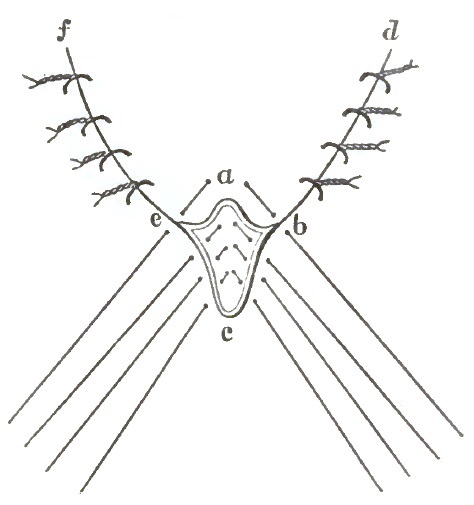

| 12. | DIAGRAM OF EMMET'S OPERATION |